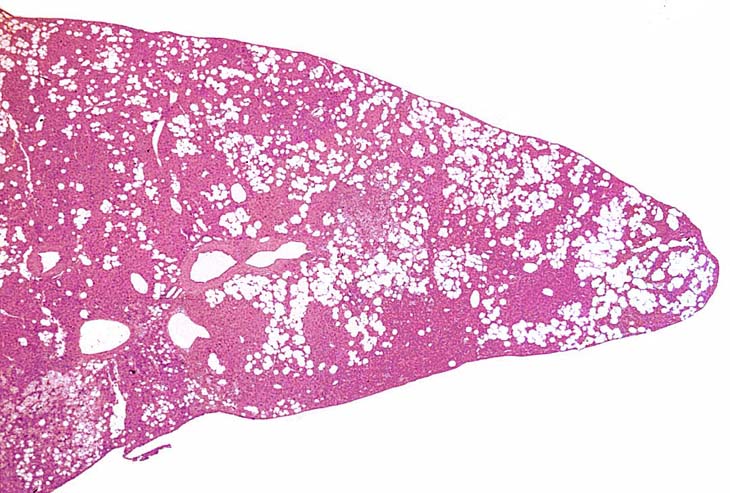

A relative discrete Ito cell tumor is present within this hepatic lobe; a higher magnification shows proliferation of stellate cells within the hepatic sinusoidal spaces.